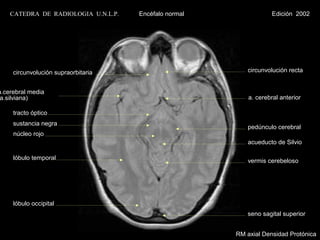

circunvolución supraorbitaria                        circunvolución recta

a.cerebral media

a.silviana)                                               a. cerebral anterior

tracto óptico

sustancia negra

pedúnculo cerebral

núcleo rojo

acueducto de Silvio

lóbulo temporal                                      vermis cerebeloso

lóbulo occipital

seno sagital superior

RM axial Densidad Protónica